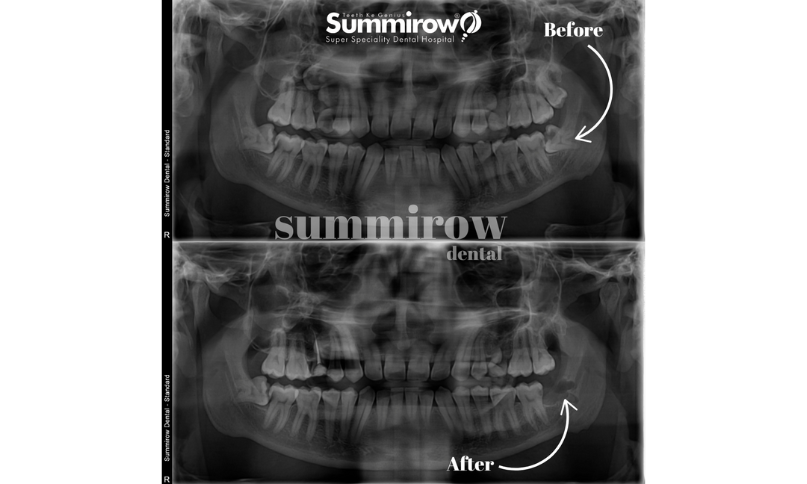

We use in house advanced digital imaging (OPG/CBCT) and minimally invasive techniques to assess, plan, and perform disimpactions safely and efficiently.